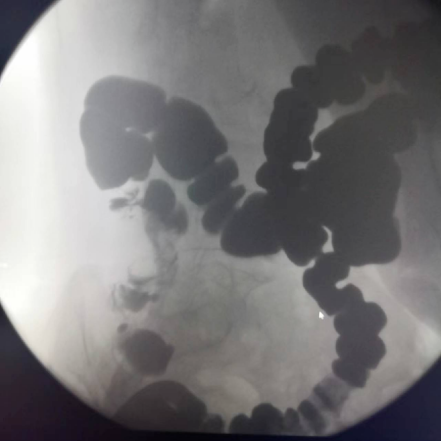

下消化道造影

能顯示空腸、回腸及結(jié)腸的影像,能清晰診斷腸套疊、直腸結(jié)腸息肉、憩室等病變。